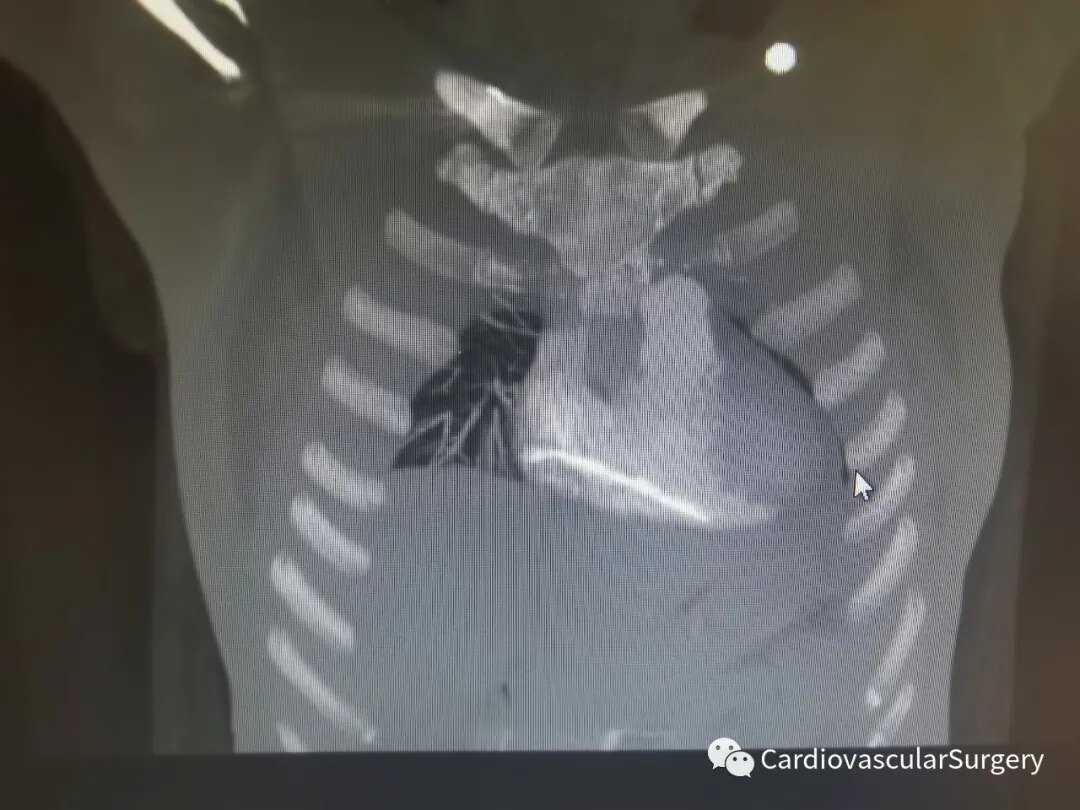

患者入院后,我们立即行心脏超声检查,发现右房、右室内见一长约78mm,直径约3mm条状强回声。右室条状强回声紧贴心尖处室间隔右室面。三尖瓣瓣叶正常,舒张期开放无受限。肺动脉CTA发现异物位置与心超相同(图如下)。

明确心脏内异物的位置及大致形态,并完善必要检查及化验后,励峰主任团队决定尽快手术,在全麻体外循环下行心脏切开异物取出术,术中探查可见,骨水泥通过三尖瓣口,与心脏长轴平行位于右心房和右心室之间,部分骨水泥已与心房壁组织粘连并覆盖一层纤维组织,需要游离才可完整取出,但异物未损伤三尖瓣结构:(术中)